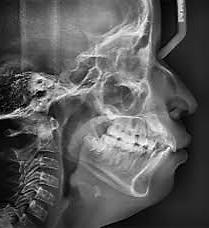

El seguimiento del trayecto canino con un estudio radiográfico postero anterior, lateral de cráneo y ortopantomográfico, a partir de la edad señalada anteriormente, también es una herramienta efectiva que permite obtener un diagnóstico inicial, donde podrá observarse si se ha iniciado la reabsorción radicular del canino deciduo e identificar qué

dirección o trayecto está tomando el canino permanente (Figura 18).

propósito de ubicar al canino con posibilidades de incluirse, en su trayectoria de erupción, está el desarrollado por el Dr. Ricketts, 5 que además de ser una herramienta para planificación de un tratamiento interceptivo ortodóntico adecuado, permite visualizar y el trayecto de formación y erupción del canino, esto es, utilizando radiografías laterales de cráneo, aplicando la técnica de superposición (Figura 23).

Este método es el más utilizado en la actualidad7 y se complementa con un área de estudio que detecta cambios dimensionales y de dirección de crecimiento, tanto en el maxilar como en la mandíbula.6 El apoyo de este análisis, es el punto de partida para tomar acciones interceptivas, en beneficio de obtener los espacios suficientes para el acomodo de caninos y de ese modo evitar su inclusión.